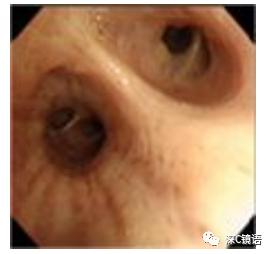

为了准确诊断肺部和支气管等呼吸系统疾病,将支气管镜通过口或鼻腔,经咽喉部插入气管和支气管,观察管腔和组织并收集样本(例如分泌物和细胞)的一种检查。在气管分支为左支气管和右支气管之后,每个分支进一步重复分支,直至到达控制呼吸的肺泡。支气管的每次分支都会变细,使用支气管镜可以观察支气管的内腔,通常将其称之为段支气管,直径约为5毫末。如果您有以下症状或发现,我们建议进行支气管镜检查: 3.当胸部X线或CT扫描显示肺部异常阴影,并且怀疑肿瘤或结核时 3.检查过程中,您需要吸氧,并连接监测仪器进行心电和血脉氧监测。4.当您平卧在床上后,支气管镜将从口腔或鼻腔进入,经过喉咙进入气管支气管。如果是从口腔入镜,则需要将咬口器放到嘴里。如果是从鼻腔入镜,则对鼻腔进行局部麻醉。 5.通过观察支气管来确认病变是否存在。如果过程中出现咳嗽,则在支气管内再次进行局部麻醉。在检查过程中,你可以正常呼吸,但由于支气管镜穿过声门所以无法发出声音。如果您有任何异常不适,请及时向医生发出信号(例如使用手势)告知我们。检查期间,放松肩膀并轻柔呼吸。切勿触摸支气管镜或其他仪器,因为这存在危险。 6.另外,为了明确诊断,可能需要从适当的区域收集细胞和组织。 7.确保没有出血等并发症,可移除支气管镜并结束检查。检查时间通常为20至30分钟,根据检查和治疗内容的不同,所需的时间也有不同。8.咽喉部麻醉效果不会立即消失,检查后2小时内请勿喝水和进食。根据检查的内容,可能会出现以下并发症,如有出现并发症可能需要进一步的手术和医疗措施。1.肺和支气管出血(发生率0.66%):当收集细胞和组织学样本时,总是伴有少量出血。通常少量出血能自行止血,但在极少数情况下,出血无法自行停止,需根据情况采取干预措施。包括注射止血药物或插入封堵器以阻塞出血的支气管。更严重的情况可能需要紧急气管插管。 2.气胸(发生率0.4%):组织活检时,肺部的脏层胸膜可能会受损,如果空气从受损处泄漏,则可能导致“气胸”并压迫肺脏。这种情况的气胸通常较为缓和,只需要休息几天。当合并肺气肿等基础病变时,气胸可能会持续漏气,因此而需要进行胸腔闭式引流术。 3.发热和肺炎(发生率0.22%):检查后很少发生,即使发生大多数也是暂时性的,根据情况可能需要使用抗生素。 4.麻醉药引起的过敏或中毒(发生率0.04%):在极少数情况下,局部麻醉药利多卡因可能会发生过敏反应。出现时需立即停止支气管镜检查并进行相应处理。过量的麻醉药物可能引起中毒症状(焦虑,兴奋,头晕,血压下降,心律不齐,抽搐等)。这些症状一般会随着时间流逝和药物的代谢而消失。 5.其他:比较罕见如哮喘(发生率0.07%),呼吸衰竭(发生率0.09%),心肌梗塞心律不齐等其他心血管疾病(发生率0.07%),支气管阻塞(发生率0.02%),以及非常罕见的意外事故导致的死亡(发生率0.004%)。很遗憾的是,目前无法通过CT,MRI,PET等影像手段来获得肺部病变的明确诊断。可替代支气管镜的方法包括以下内容。 1.CT引导的肺活检:主要针对肺部病变。在CT确认病变确切位置的同时,在局部麻醉下,将一根细针刺入胸部以从病变中收集样本。这种方式的气胸等风险增加,住院时间可能更长。 2.手术活检:包括胸腔镜活检和开胸活检。两者均需要在全身麻醉下进行。胸腔镜活检通常需要在胸部皮肤上做1-3个切口,胸腔镜插入胸腔后观察的同时切除病灶并收集样本。开胸活检需要打开胸腔进行观察和病灶切除。两种方法的诊断率都很高。 3.纵隔镜活检:主要用于纵隔肿大淋巴结或纵隔肿块的活检。需要在全身麻醉下进行,从胸骨上方的皮肤切口插入纵隔镜,观察纵隔内部并收集样本。并发症包括出血和声音嘶哑等。以下(常见但不限于)方法可经支气管镜对支气管和肺疾病进行治疗。 1.热消融术(高频电,微波,激光,氩等离子体凝固)